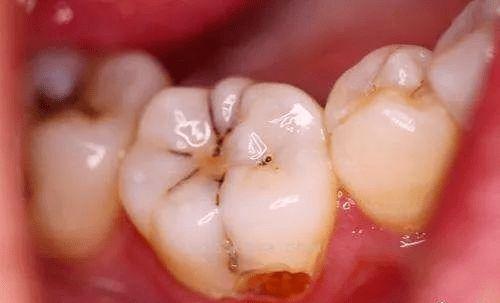

蛀牙的發(fā)展是一個(gè)漸進(jìn)的過程。首先,細(xì)菌在牙齒表面形成一層薄薄的菌斑,菌斑中的細(xì)菌代謝食物中的糖分產(chǎn)生酸。這些酸會(huì)使牙齒表面的礦物質(zhì)溶解,形成早期的齲損,也就是我們常說的“小黑點(diǎn)”或“小白斑”。如果此時(shí)不加以處理,齲損會(huì)逐漸加深,侵入牙本質(zhì),形成中齲或深齲。